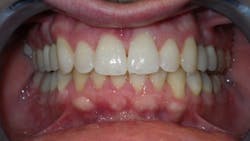

Primary issues

- He measured 28 mm, which is very narrow considering that uncrowded adults measure 35 mm–39 mm.